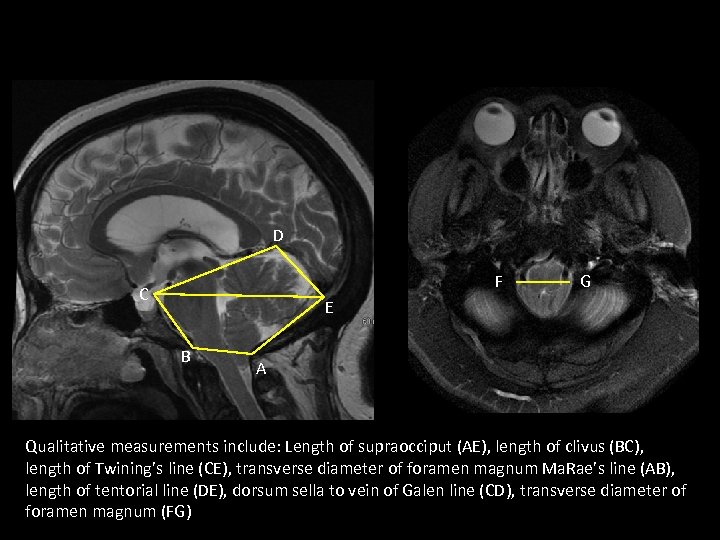

D F C G E B A Qualitative measurements include: Length of supraocciput (AE), length of clivus (BC), length of Twining’s line (CE), transverse diameter of foramen magnum Ma. Rae’s line (AB), length of tentorial line (DE), dorsum sella to vein of Galen line (CD), transverse diameter of foramen magnum (FG)

D F C G E B A Qualitative measurements include: Length of supraocciput (AE), length of clivus (BC), length of Twining’s line (CE), transverse diameter of foramen magnum Ma. Rae’s line (AB), length of tentorial line (DE), dorsum sella to vein of Galen line (CD), transverse diameter of foramen magnum (FG)